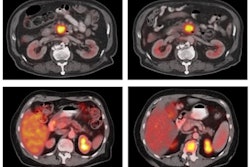

Researchers imaged 10 tissue graft models of glioma and renal cell carcinoma with F-18 TRX to measure LIP. They measured the uptake of the radiotracer in the cancer. An animal model study was also conducted to determine effective human dosimetry.

(A) F-18 TRX PET/CT data showing radiotracer uptake in a U87 MG tumor (arrow) implanted within the right hemisphere of a mouse brain. The image was acquired at 90 minutes post injection. (B) Quantification of F-18 TRX uptake using ROI analysis of the PET data from mice bearing U87 MG tumors (n = 3). The tumor uptake was compared to uninvolved normal white matter on the contralateral region of the brain. (C) Digital autoradiography showing the distribution of the radiotracer within a coronal section of the mouse brain. The tissue was stained with H&E and merged with the pseudocolor image of the autoradiography. Image courtesy of the Journal of Nuclear MedicineF-18 TRX showed a wide range of tumor accumulation but successfully identified LIP levels among tumors and helped determine which ones might be most likely to respond to LIP-targeted therapies. The estimated effective dose for adults was comparable to doses used with other F-18 tracers.